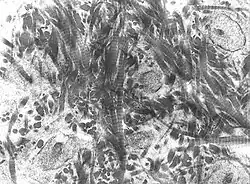

Collagen fibers of woven bone

Collagen fibers of woven bone Osteoclast displaying many nuclei within its "foamy" cytoplasm.